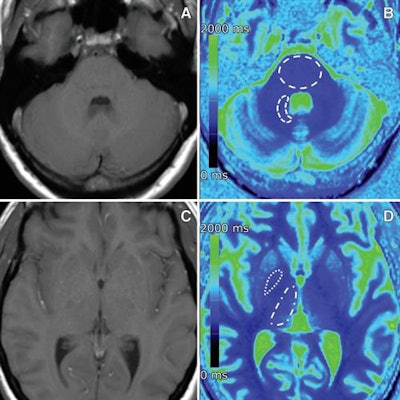

There were no differences in MRI signal intensity between patients who received at least five doses of the macrocyclic gadolinium-based contrast agent (GBCA) gadobutrol (Gadavist, Bayer HealthCare) and controls who had no GBCA exposure; however, there was a significant difference in T1 relaxation times in one particular brain region.

All 220 subjects underwent unenhanced MRI brain scans on a 1.5-tesla MRI scanner (Magnetom Aera, Siemens Healthineers). The protocol included T1-weighted spin-echo and T1 and T2 mapping to determine visual signal-intensity changes; signal-intensity ratios of the globus pallidus to the thalamus and the dentate nucleus to the pons; and T1 and T2 relaxation times. In MRI terms, relaxation refers to how signals can weaken or broaden over time. T1 mapping helps calculate the loss of signal, while T2 mapping conveys broadening of the signal.

The results showed no visual changes or differences in signal-intensity ratios or in T1 and T2 mapping between the patient groups.

However, there were significantly shorter T1 relaxation times in the globus pallidus among patients with normal renal function and multiple administrations of gadobutrol, compared with control subjects with normal renal function. The difference between the two groups was 226.2 msec (p = 0.002).